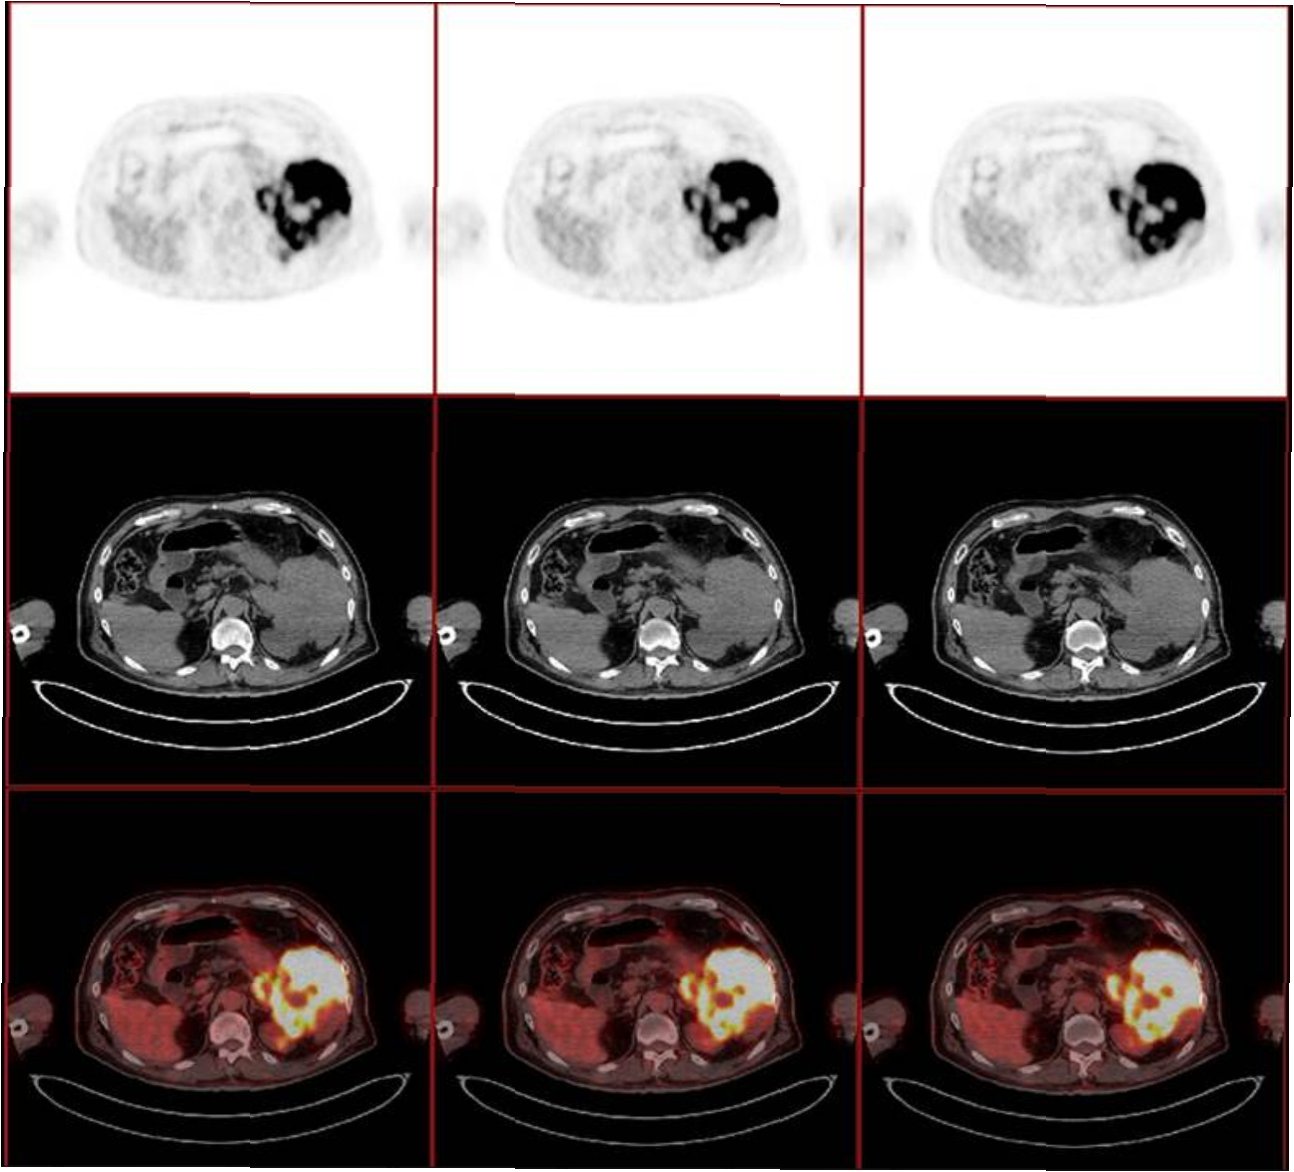

그러다 임신 14주 차 직장에서 쓰러져 병원으로 실려간 뒤 정밀검사에서 원발성 종격동 B세포 림프종(Primary Mediastinal B-cell Lymphoma, PMBCL)을 진단받았다. 종양은 심장 크기만큼 자라 있었고, 빠르게 진행되는 특성상 즉각적인 항암치료가 필요했다. 항암제를 투여할 경우 태아 생존은 불가능했다.

소피아가 진단받은 원발성 종격동 B세포 림프종(PMBCL)은 비교적 드문 형태의 혈액암으로, 비호지킨 림프종의 아형에 속한다. 이 암은 면역세포인 B세포에서 발생하며 주로 가슴 중앙부에 위치한 종격동에서 발병한다.